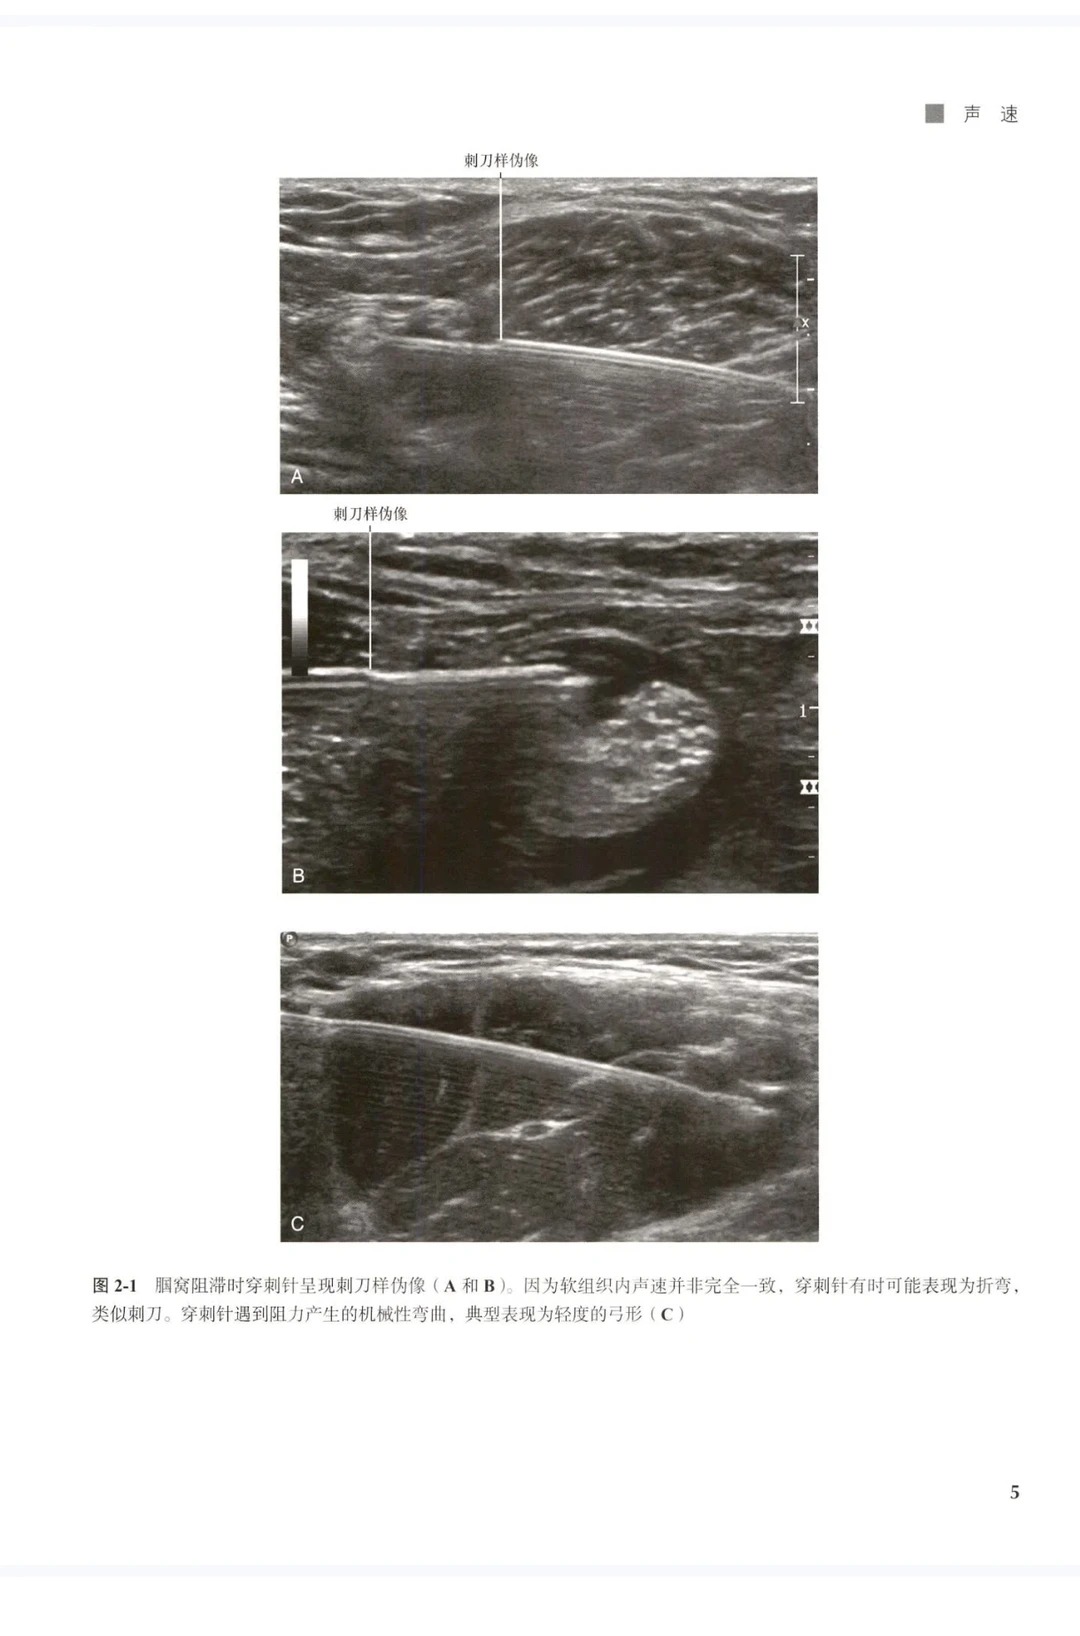

3.  高清直观,操作更轻松 收录超500幅高清体表+超声对照图,清晰呈现解剖变异、穿刺路径、神经定位细节,将抽象的解剖结构与超声图像精准对应,告别“看不清、找不准”的难题,新手能快速上手,老手能精准规避风险。